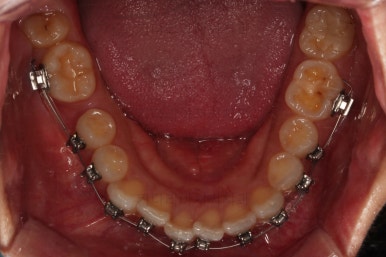

3. 치료경과

장치를 부착했고요.

이번에 환자분이 선택한 장치는 윗니는 자가결찰 세라믹, 아랫니는 자가결찰 메탈이었습니다.

이렇게 혼용해서 사용해도 되는 조합들이 있고요.

이번 환자분은 웃을 때 이가 많이 보이는 타입이 아니셔서 아랫니는 좀 더 튼튼하고 저렴하기까지한 메탈장치를 선택하셨죠.

아랫니는 어금니와 사랑니를 앞으로 당겨옵니다.

물론 다른 치아에 변화를 주지 않기 위해서 미니스크류를 이용합니다.